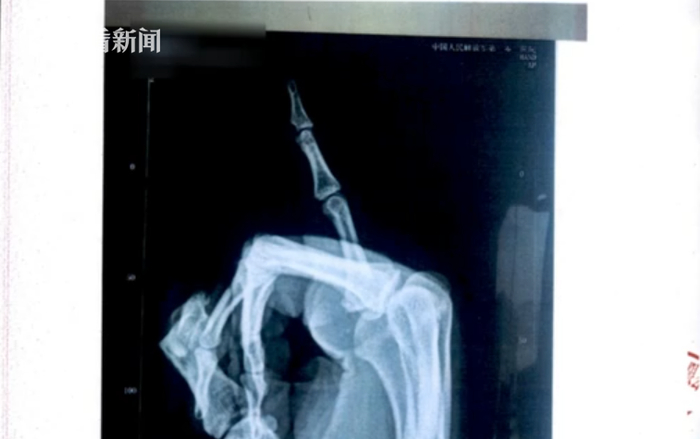

经过深入研判分析,民警发现这应该是一个10余人的诈骗团伙。从2019年下半年开始,该团伙在江苏省内各地流窜作案。他们会先让团伙中的某个成员去当地的企业上班,入职后没几天,这名成员就会使用砖头、木棍、千斤顶等工具把小拇指敲断,制造出伤情后,其他成员就接续登场了。

扬名派出所民警徐真锴:“由这个受伤的人骑电瓶车,其他人开车,然后伪造一个相撞的事故,然后在这个过程中呢,他们事先就约定好,在交警来了之后,由这个驾驶(汽车的)一方完全把责任认下来,因为在这个工伤赔偿条例当中,只有自己在无责的情况下才能够进行这个工伤的赔偿,所以他们在跟我们交警同志陈述的过程中,就是以自己开车玩手机啊,或者说开车打瞌睡为由,把这个责任全部承担下来。”